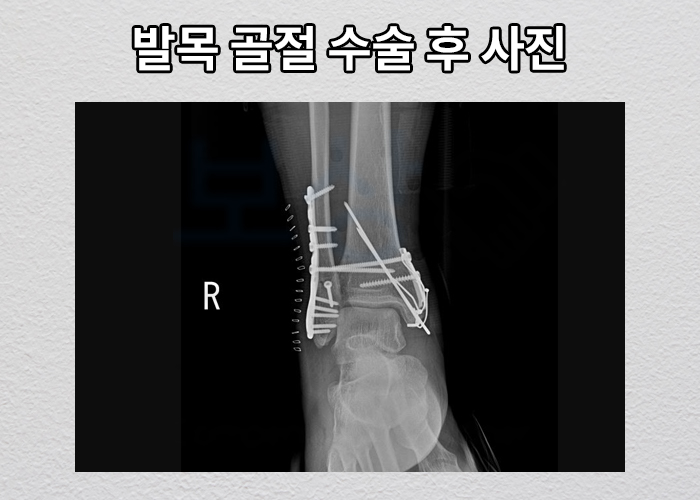

작업 발판을 설치하시던 중 1M 높이에서 발판과 함께 아래로 추락하는 사고를 당하셨습니다. 위 사고로 의뢰인은 발목에 극심한 통증을 느끼셨고, 인근 병원으로 후송되어 정밀검사 받게 되었는데요, 검사 결과, 발목의 무려** 3군데가 부러지는 삼복사골절** 다른말로는 삼과골절이라고도 합니다.

금속 핀과 플레이트로 고정하는 수술을 받으셔야 했죠. 산재보험 처리해서 얼마나, 어떻게 보상 받을 수 있을까요?